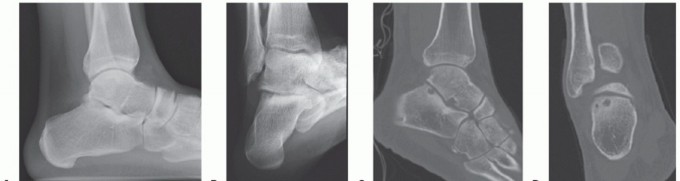

DEFINITION Posterior ankle impingement syndrome is a clinical disorder characterized by posterior ankle pain …

DEFINITION Because of their nature and deep location, posterior ankle problems pose a diagnostic and therapeu…